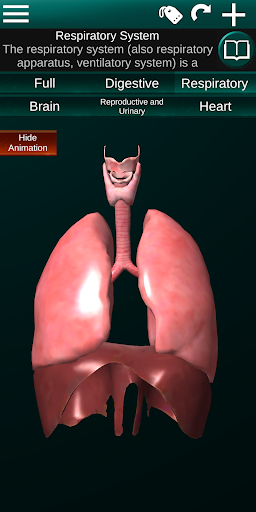

Toont een 3D-anatomisch model van de belangrijkste organen van het menselijk lichaam en een beschrijving van elk orgaan.

* Ademhalingssysteem, inclusief de luchtpijp, bronchiën, longen en een animatie van dit systeem.